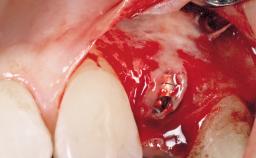

Immediate Flapless Placement of an Implant in a Maxillary Left Central Incisor Site

A 29-year-old female patient presented for treatment to replace the upper left central incisor tooth with an implant- supported restoration. The tooth had been intermittently symptomatic for the previous 12 months. The tooth had originally suffered trauma about 15 years previously. Several endodontic treatments had been performed, including an apicectomy procedure to retain the tooth. The patient was healthy and a non-smoker. She had reasonable expectations in regard to esthetic outcomes and the risk of marginal tissue recession following treatment. At medium smile, the gingival margins of the upper teeth were visible, with a display of 3 to 4 mm of the gingival margins. Gingival recession of tooth 21 and a discrepancy in the gingival levels between teeth 11 and 21 was observable during normal speech and smile.

| Placement Protocol | Immediate implant placement |

| Socket Integrity | Damage to one or more bone walls |

| Bone Volume | Damage to one or more socket walls |